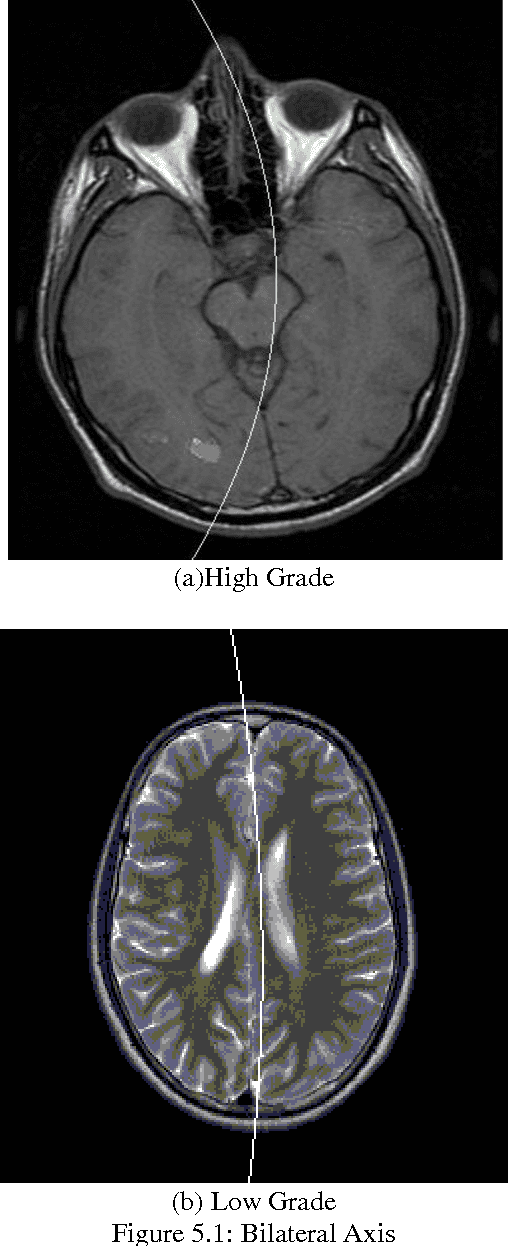

Abstract:Image segmentation some of the challenging issues on brain magnetic resonance image tumor segmentation caused by the weak correlation between magnetic resonance imaging intensity and anatomical meaning.With the objective of utilizing more meaningful information to improve brain tumor segmentation,an approach which employs bilateral symmetry information as an additional feature for segmentation is proposed.This is motivated by potential performance improvement in the general automatic brain tumor segmentation systems which are important for many medical and scientific applications.Brain Magnetic Resonance Imaging segmentation is a complex problem in the field of medical imaging despite various presented methods.MR image of human brain can be divided into several sub-regions especially soft tissues such as gray matter,white matter and cerebra spinal fluid.Although edge information is the main clue in image segmentation,it cannot get a better result in analysis the content of images without combining other information.Our goal is to detect the position and boundary of tumors automatically.Experiments were conducted on real pictures,and the results show that the algorithm is flexible and convenient.